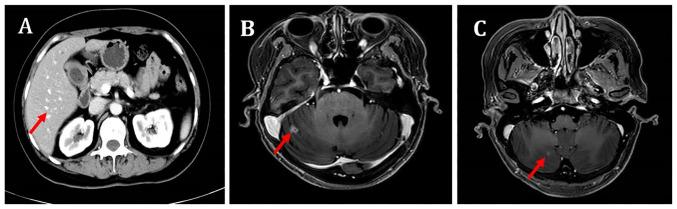

For patients with hormone receptor-positive (HR) and human epidermal growth factor receptor 2-negative (HER2) metastatic breast cancer (mBC), the treatment choices become more complex after progression on first-line CDK4/6 inhibitors combined with endocrine therapy. Currently, there are no guidelines that provide a unified standard protocol for this situation. Almost half of patients with mBC develop brain metastases (BMs), and once BMs occur, the survival of the patient is often significantly reduced. An anti-angiogenic drug and chemotherapy combination of has demonstrated synergistic effects in an mBC cell line. Anti-angiogenic drugs have shown therapeutic efficacy in the treatment of mBC, and utidelone has shown the ability to cross the blood-brain barrier and achieve a high concentration in brain tissue in preclinical studies. The present case report describes a patient with HR/HER2 mBC and BMs that developed resistance to two CDK4/6 inhibitors and treatments with anthracyclines/taxanes. The patient received a fourth-line treatment regimen combining utidelone with a small-molecule anti-angiogenic drug, namely apatinib or anlotinib. The patient achieved a partial response with this combined regimen, and a progression-free survival (PFS) of 7.6 months, which was the best therapeutic outcome in the entire course of the illness. This result was superior to the second-line treatment with nab-paclitaxel, which resulted in a PFS of 8 months and best overall response of stable disease with slight shrinkage. The present case indicates that a combination of utidelone with apatinib/anlotinib exhibited antitumor activity in a patient with HR/HER2 mBC with BMs. Therefore, this combination offers a promising therapeutic option for the clinical treatment of patients with breast cancer and BMs.

对于激素受体阳性(HR)且人表皮生长因子受体2阴性(HER2)的转移性乳腺癌(mBC)患者,在一线CDK4/6抑制剂联合内分泌治疗进展后,治疗选择变得更加复杂。目前,尚无指南针对这种情况提供统一的标准方案。几乎一半的mBC患者会发生脑转移(BMs),一旦发生BMs,患者的生存期通常会显著缩短。抗血管生成药物与化疗联合在一种mBC细胞系中已显示出协同作用。抗血管生成药物在mBC治疗中已显示出治疗效果,在临床前研究中,优替德隆已显示出能够穿过血脑屏障并在脑组织中达到高浓度。本病例报告描述了一名患有HR/HER2 mBC和BMs的患者,该患者对两种CDK4/6抑制剂以及蒽环类/紫杉类治疗产生了耐药性。该患者接受了优替德隆与小分子抗血管生成药物(即阿帕替尼或安罗替尼)联合的四线治疗方案。该联合方案使患者获得了部分缓解,无进展生存期(PFS)为7.6个月,这是整个病程中的最佳治疗结果。该结果优于二线白蛋白结合型紫杉醇治疗,后者的PFS为8个月,最佳总体反应为疾病稳定且有轻微缩小。本病例表明,优替德隆与阿帕替尼/安罗替尼联合在一名患有HR/HER2 mBC和BMs的患者中表现出抗肿瘤活性。因此,这种联合为乳腺癌和BMs患者的临床治疗提供了一种有前景的治疗选择。